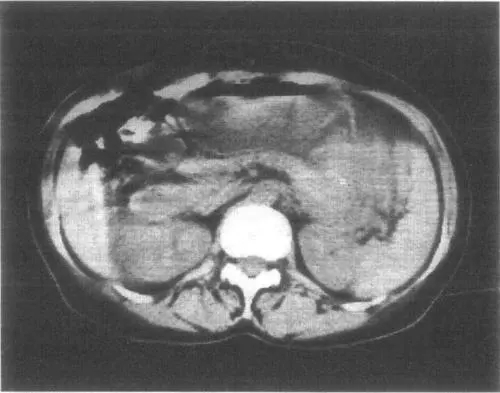

1.3.CT掃描顯示 腫瘤位于后縱隔,多靠近椎旁,腫瘤邊界清楚。呈圓形、卵圓形,良性或惡性腫瘤部分病例可以有分葉。多發(fā)性神經(jīng)纖維瘤病,CT掃描的檢出率往往比普通X線胸片高。

1.4.磁共振成像(MRI) 增強的T1和T2的影像可顯示:神經(jīng)纖維瘤有一高密度特征性外周區(qū)和中等密度的中央?yún)^(qū),而神經(jīng)鞘瘤為不均質的高密度區(qū)。CT或MRI可以確定,腫瘤侵入脊椎管的情況,后者還可以用來確定累及范圍。然而目前通常使用增強的脊髓X線檢查來了解腫瘤入侵的情況。如為一側胸內巨大神經(jīng)源性腫瘤,X線片、CT片均可顯示巨大腫瘤占滿整個胸腔,縱隔向健側移位,氣管移位,受壓或變窄,患側肺受壓,常見患側胸內積液。